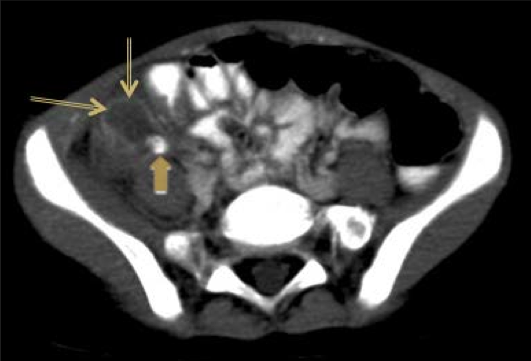

A 43-year-old male was admitted to the hospital because of repeated episodes of syncope. He had passed bloody stools over the past several months and had experienced intermittent episodes of diarrhea and constipation. A rectal exam was negative. Hematocrit was 24% with an MCV of 67 mm (fL). The stool was guaiac positive, 3+. Sigmoidoscopic exam revealed an almost encircling and ulcerated plaque-like lesion at 20 cm. Where is this patient at highest risk for metastatic cancer?

Liver is the most common site of metastasis for colonic adenocarcinoma.